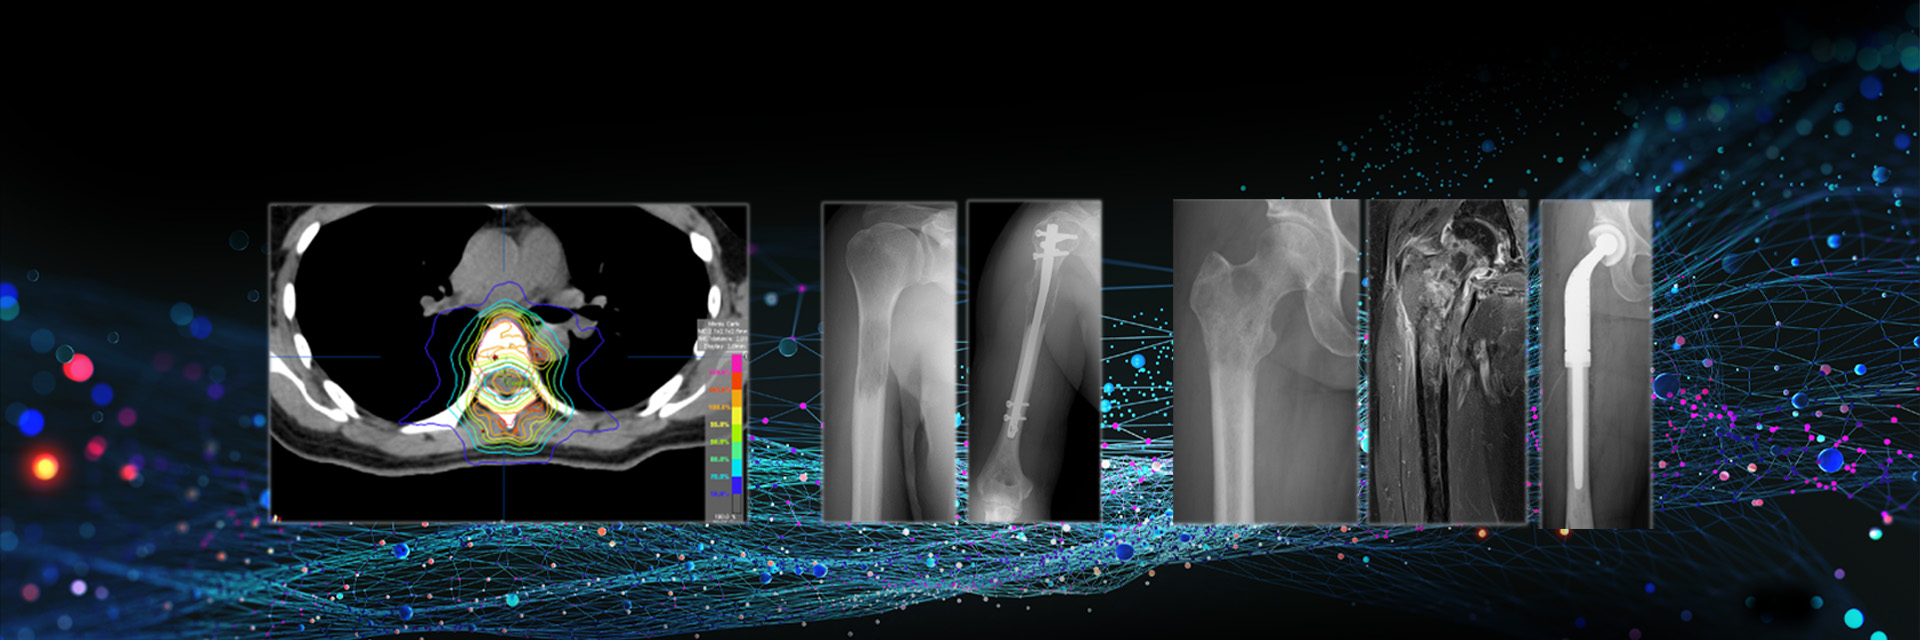

がんになっても痛みなく

動けるように

骨転移を集学的に診療し

生活の質の改善を

目指します